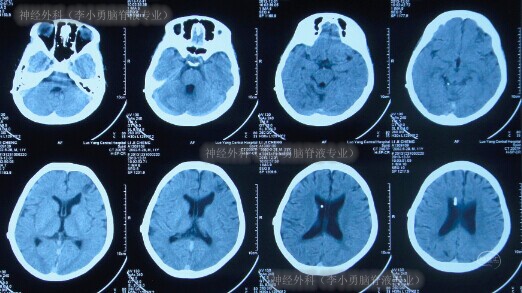

术后好转出院,出院时头颅CT示脑室显著缩小至基本正常(图-8)。

图-8:2013年12月31日头颅CT

入院次日即2014年8月1日,查头颅CT(图-12)示脑室系统稍扩张(外院拔除脑室外引流后1天)。

图-12:2014年8月1日头颅CT

在术后第4天即2014年8月5日,查头颅CT示脑室较术前稍缩小(图-13)。

图-13:2014年8月5日头颅CT

住院21天即2014年8月20日,查头颅CT(图-14)后按计划进行了左侧侧脑室腹腔分流术。

图-14:2014年8月20日头颅CT